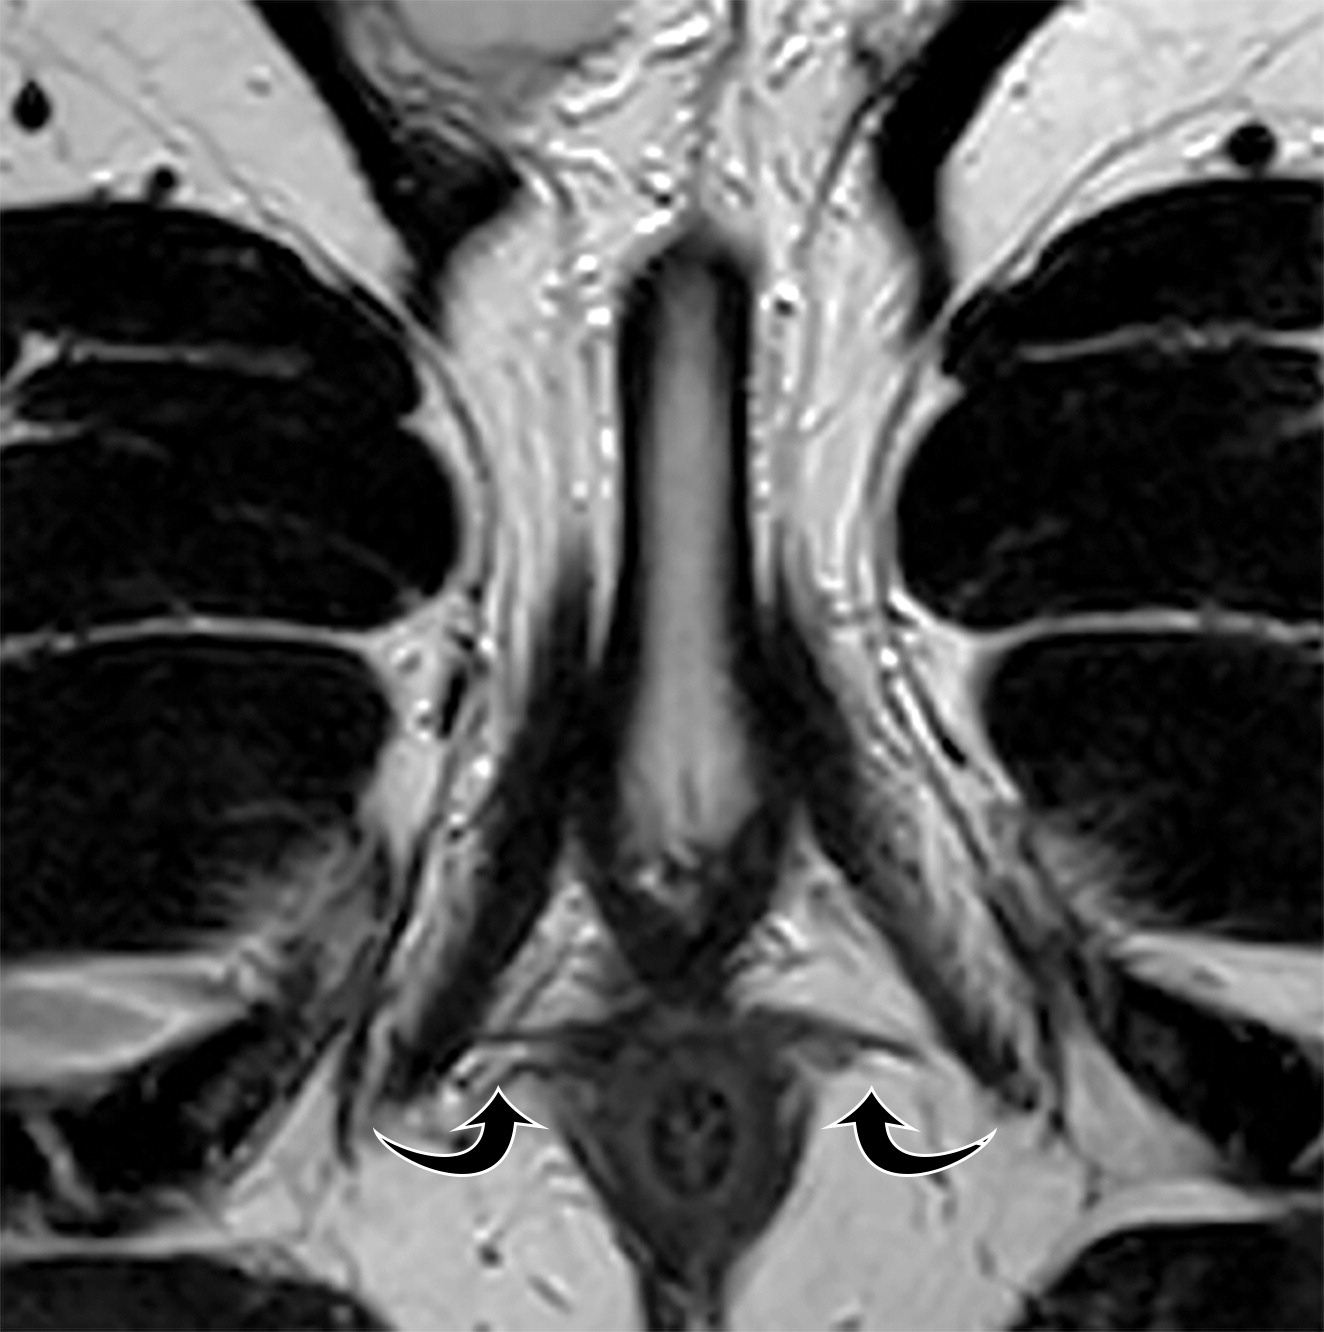

(上图)70岁男性,轴位T2WI示右侧会阴横肌的瘢痕及增厚(上图黑色短箭头),左侧会阴横肌相对萎缩(上图黑色长箭头)。

(下图)40岁无症状男性,轴位T2WI示正常的解剖结构(下图弯曲黑色箭头)。